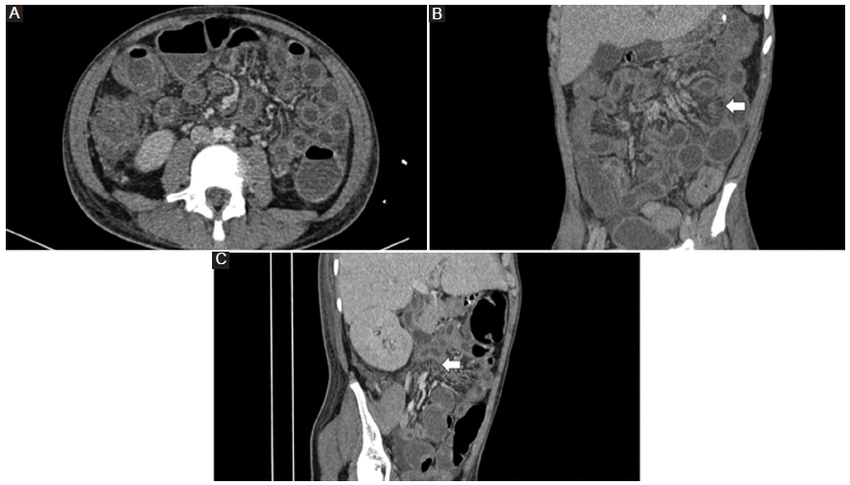

En cuanto al engrosamiento de las paredes intestinales que se puede asociar al signo del peine, tampoco es específico para la EC y también se puede observar en la colitis ulcerativa, la enteritis por radicación, algunas infecciones, la gastroenteropatía eosinófila, la enfermedad celiaca, la isquemia intestinal crónica y la enfermedad del injerto contra el huésped (Fig. 3) (2.